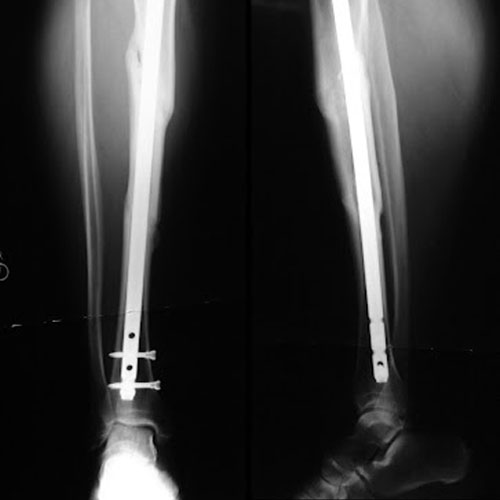

A bone fracture that is not currently healed and which will not even heal in the future is known as non-union. The non-union fractures are defined when there is no 9-month post occurrence or healing and has not shown any progress for three months.

Recovery and hospital stay at orthopedic hospital of a patient depends on the healing progress after orthopedic surgery which is determined by doctors by taking X-rays.